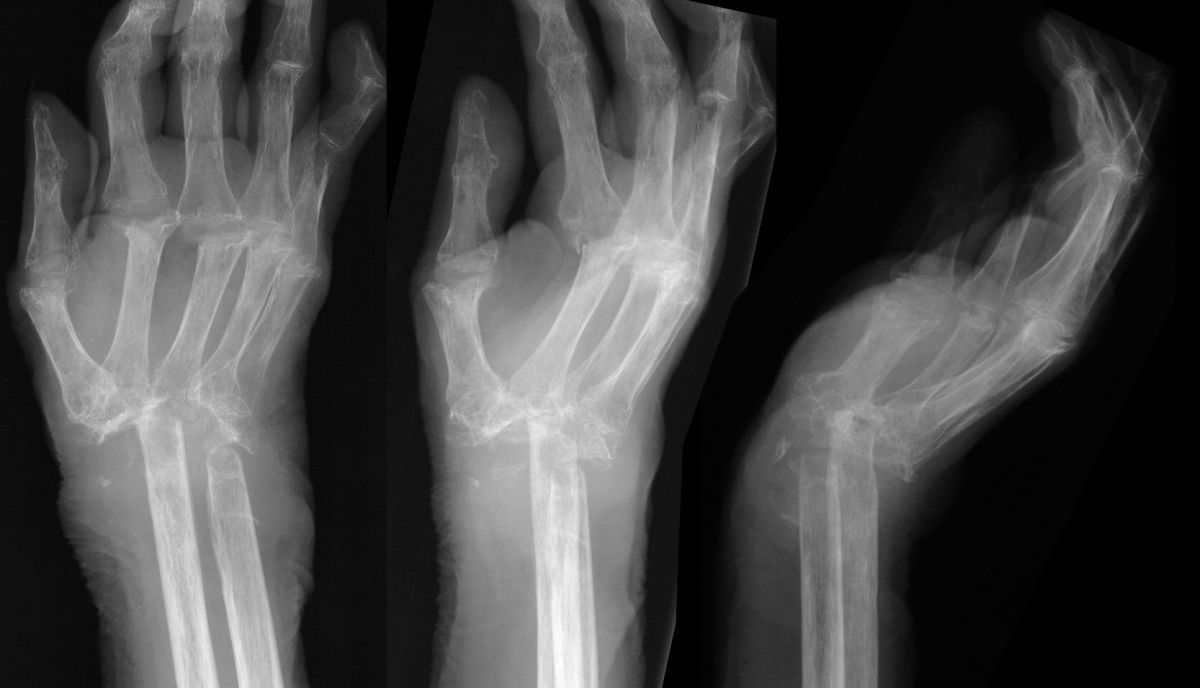

There was no cinical evidence of residual infection. She maintained a functional range of motion from her pseudoarthrosis and did not wish to have any more surgery.

Highslide

Four years later, she complained of wrist instability, and xrays confirmed intermittent radiometacarpal dislocation.